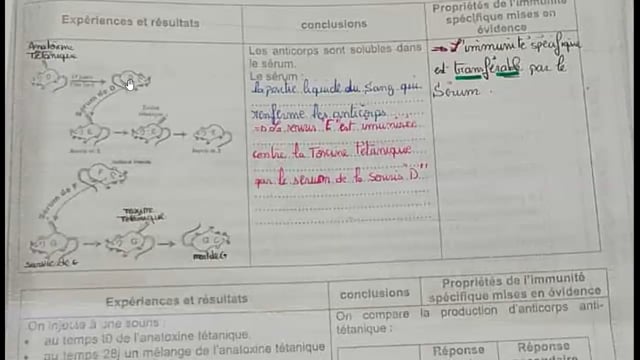

Sciences SVT